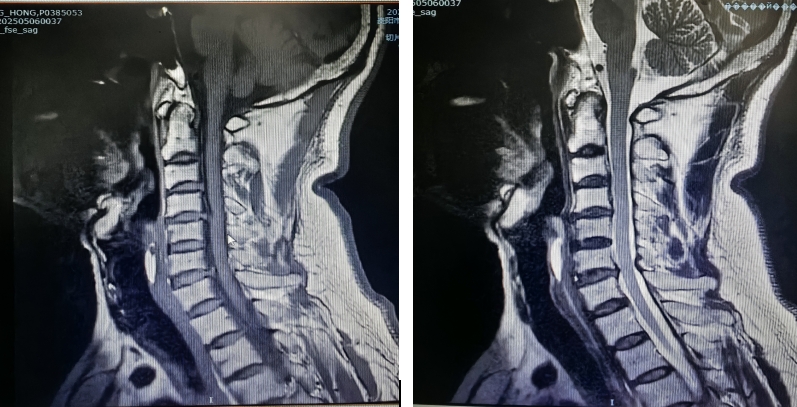

患者因"頭痛、雙上肢麻木伴下肢乏力1月"入院,此前長期保守治療效果不佳,癥狀持續(xù)加重并出現(xiàn)行走不穩(wěn)。經(jīng)多學科聯(lián)合會診,團隊決定采用國際先進的零切跡cage融合術。手術歷時2小時,出血量僅10ml,術后患者即刻感到頸部及肢體癥狀顯著緩解,術后三天即可下床活動,微創(chuàng)切口(3—4厘米)及快速康復效果獲家屬高度贊譽。